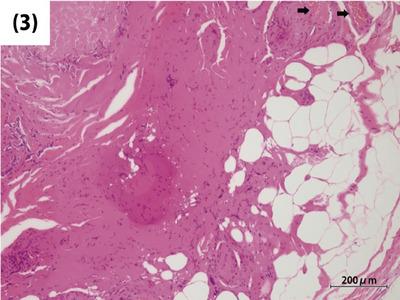

Perivascular epithelioid cell tumor (PEComa) is a rare mesenchymal tumor. Some papers have reported that colonoscopy could be used to treat PEComa with a predominantly pedunculated polyp, whereas surgical intervention is often required for cases with submucosal-type tumors. These findings suggest that the morphology of PEComa changes dramatically with disease progression. Because of the rapid progression of PEComa, endoscopic treatment remains challenging, and early-stage PEComa morphology is not well understood. A 64-year-old man presented to our hospital for a follow-up colonoscopy after undergoing multiple polypectomies. He had a medical history of colorectal adenoma and prostate cancer. A 4-mm pale blue elevated but not pedunculated lesion was observed in the transverse colon, an area where he had not had polyps previously. Since no epithelial change was observed, the presence of a submucosal tumor, such as a gastrointestinal stromal tumor, was suspected. Cold snare polypectomy was performed, and the lesion was completely resected. Histological evaluation using hematoxylin and eosin staining identified that the submucosal tumor included thickened vascular walls and adipose tissue. Although fragmented due to significant degeneration, spindle-shaped cells staining positive for smooth muscle actin were observed within and surrounding the unstructured hyalinized tissue with calcifications. Based on these findings, the lesion was diagnosed as angiomyolipoma, a subtype of PEComa. Complete resection was confirmed by histopathology. To our knowledge, this PEComa is the smallest of any PEComa reported in the literature. Our finding provides valuable insights into the very early stage of colorectal PEComas.

血管周上皮样细胞肿瘤(PEComa)是一种罕见的间叶组织肿瘤。一些文献报道,结肠镜检查可用于治疗以带蒂息肉为主的PEComa,而对于黏膜下型肿瘤病例通常需要手术干预。这些发现表明,PEComa的形态会随着疾病进展而发生显著变化。由于PEComa进展迅速,内镜治疗仍然具有挑战性,而且早期PEComa的形态尚未得到充分了解。一名64岁男性在接受多次息肉切除术后到我院进行结肠镜复查。他有结肠直肠腺瘤和前列腺癌病史。在横结肠发现一个4毫米大小的淡蓝色隆起但无蒂的病变,该区域此前未发现息肉。由于未观察到上皮变化,怀疑存在黏膜下肿瘤,如胃肠道间质瘤。进行了冷圈套息肉切除术,病变被完全切除。苏木精-伊红染色的组织学评估显示,黏膜下肿瘤包括增厚的血管壁和脂肪组织。尽管由于严重变性而破碎,但在有钙化的无结构透明变性组织内及周围观察到平滑肌肌动蛋白染色阳性的梭形细胞。基于这些发现,该病变被诊断为血管平滑肌脂肪瘤,这是PEComa的一种亚型。组织病理学证实病变已完全切除。据我们所知,该PEComa是文献报道中最小的PEComa。我们的发现为结直肠PEComa的极早期阶段提供了有价值的见解。